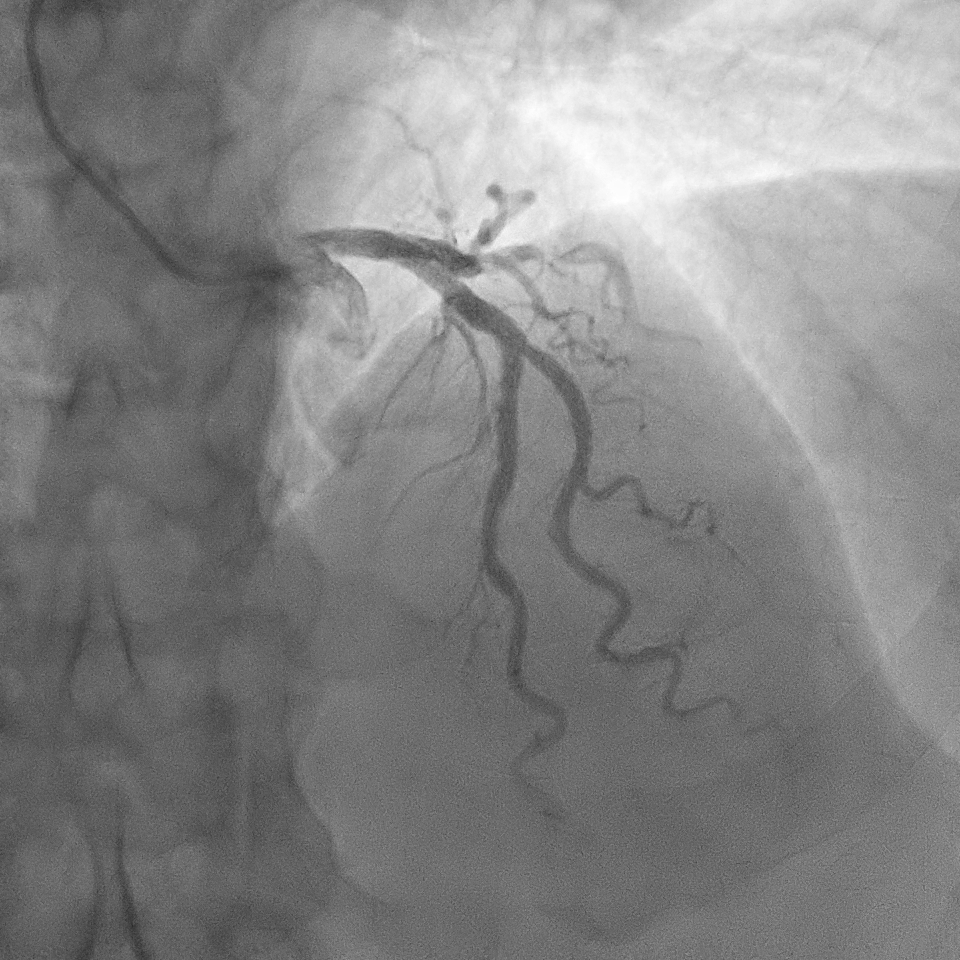

The angiogram showed right dominant system. The left main coronary artery was normal. The left anterior descending (LAD) stent was patent. There was a severe discrete stenosis at obtuse marginal branch (OM1). There was severe stenosis at mid right coronary artery (RCA) and moderate stenosis at proximal RCA.

A right radial artery approach with 6Fr sheath was used. The right coronary system was engaged with 6Fr Judkin Right (JR4) guiding catheter. The posterior left ventricular branch was wired with Runthrough NS. Intravascular ultrasound (IVUS) showed distal RCA landing zone vessel size of 4.0-4.5mm in diameter. The mid RCA showed minimal luminal area (MLA) of 1.95mm2 with fibrous plaque and calcification at 12 o'clock. The proximal RCA landing vessel size was 4.5-5.0mm in diameter. The lesion was predilated with NC Trek Neo balloon 3.0x15mm. Attempted multiple times to deliver the stent SYNERGY 4.0X48mm but failed. The stent could not be passed into proximal RCA and eventually the distal stent edge crimpled and unable to be withdrawn into the guiding catheter. Tried to pull back system enbloc into the radial artery. Attempted to pull the stent into guider but failed again. The guiding catheter was removed. The stent was left with coronary wire in situ. Exchanged 6Fr radial sheath to slender sheath and attempted to snare stent with 2.0mm snare but failed. Attempted multiple wire wrapping technique with 3 BMW wires but failed. Decided to puncture right femoral artery with 8Fr sheath. A 7Fr JR4 guiding catheter was introduced into right brachial artery. A 7mm snare then snared the stent and removed it via femoral. The lesion was predilated with Scoreflex 3.5x20mm, stented with Supraflex Cruz 4.0x48mm and post-dilated with NC balloon 4.5mm. Result was TIMI 3 and no dissection.